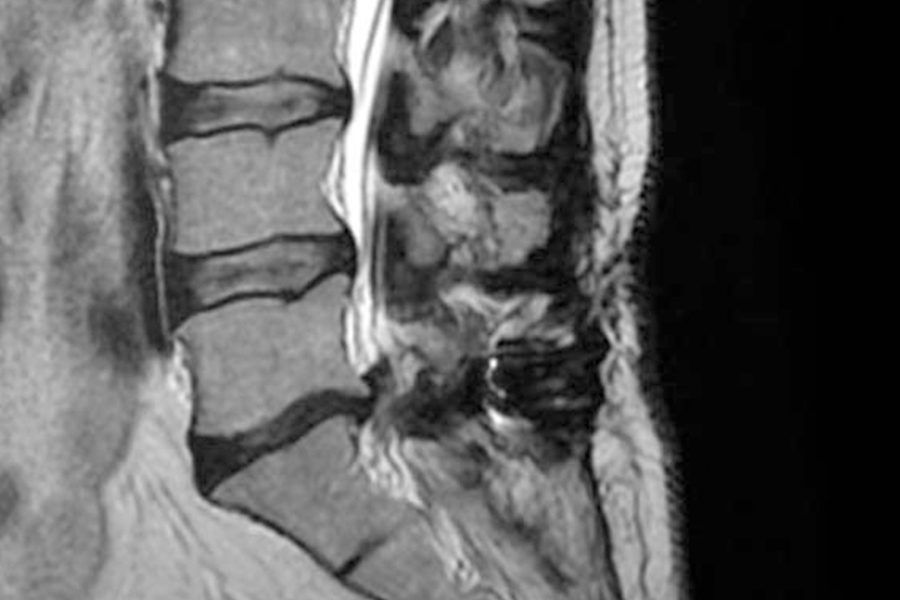

Caso clínico: endoscopia de columna multinivel L4L5 y L5S1

Los síntomas que presentaba el paciente eran dolores acentuados en las piernas, claudicación a la marcha y calambres y hormigueos en las piernas.

Durante la intervención quirúrgica, se abordarán los dos niveles mediante la técnica de endoscopia de columna.